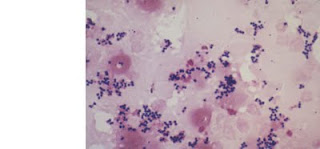

| Estreptococo beta hemolítico (microscopio normal) |

|

| Estreptococo beta hemolítico(microscopio electrónico |